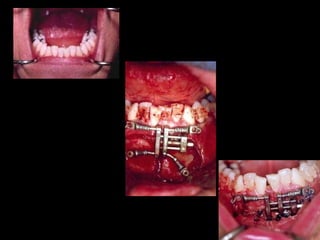

La paciente fue manejada iatrogénicamente por 5 años

Utilizando diferentes implementos ortodóncicos

La regla es clara: Laterognatias de más de 2º son quirúrgicas

24 horas de postoperatorio

La paciente fuemanejada iatrogénicamente por 5 años Utilizando diferentes implementos ortodóncicos La regla es clara: Laterognatias de más de 2º son quirúrgicas

24 horas depostoperatorio